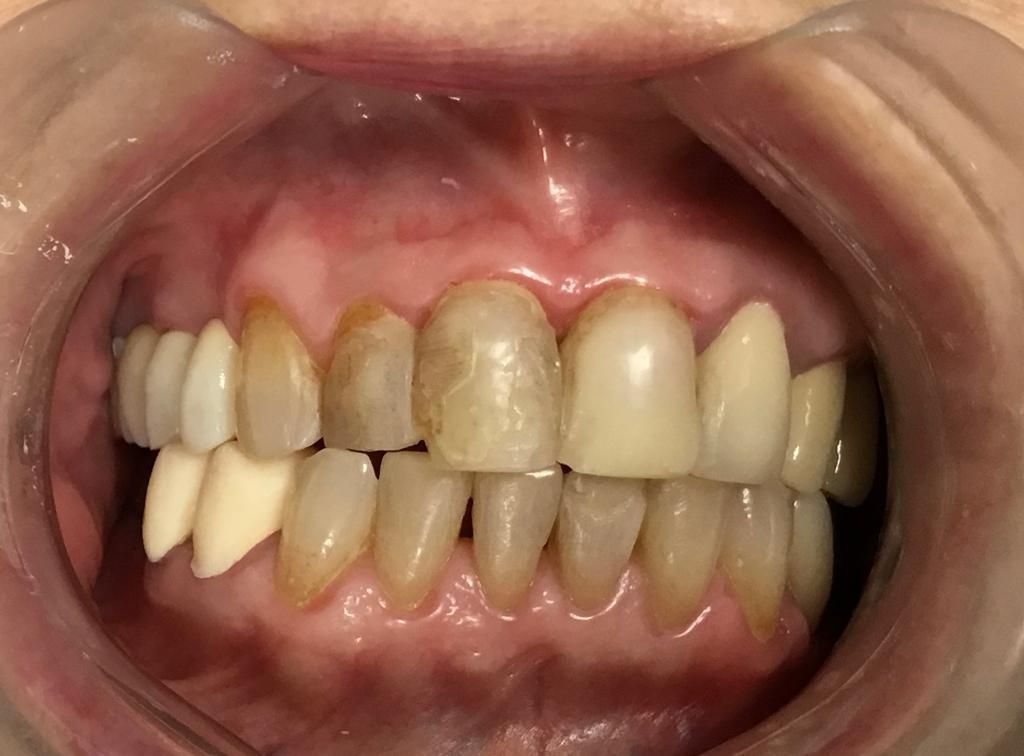

En la primera consulta se elabora un expediente clínico personalizado, respaldado por radiografías digitales y fotografías intraorales de alta precisión.

La realización de coronas dentales debe ser exclusivamente por un experto.La corona dental da protección y estética a un diente, no siempre requiere de tratamiento de endodoncia, solo en algunas ocasiones. El procedimiento requiere de mucha precisión para lograr una corona dental perfectamente bien sellada, de acuerdo a los mas recientes artículos científicos 8 de 10 coronas no sellan a la perfección.Anteriormente se realizaban coronas de metal con porcelana las cuales al cabo de un tiempo cambiaban de color y presentaban corrosión en el diente, en la actualidad contamos con diversos tipos de coronas realizadas por medio de CAD CAM zirconia, porcelana y otros materiales de alta calidad.

Desgaste dental

El desgaste dental es un padecimiento muy frecuente el cual requiere de eliminar el estimulo que origina el desgaste y restaurar la dentadura mediante diversos procedimientos ya sea resinas de alta estética o coronas de zirconia.

Se requiere una valoración con radiografías digitales y fotografías intraorales.

Diseño de sonrisa

Una alternativa inovadora para cambiar la forma y color de dientes es mediante el sistema U Venner de carillas de porcelana o de ceromero. Previamente se requiere de fotografías intraorales, toma de moldes dentales y toma de color dental. Excelente opción para diseñar una nueva sonrisa.